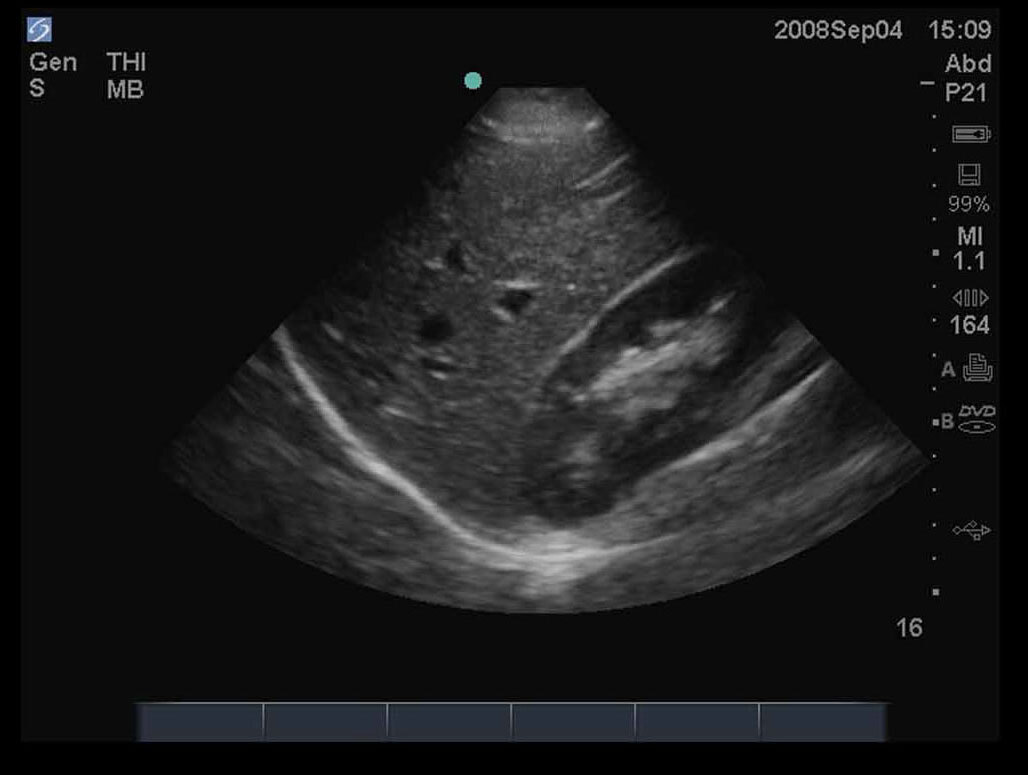

FAST Right Upper Quadrant (RUQ) 2 Image

M-Turbo.